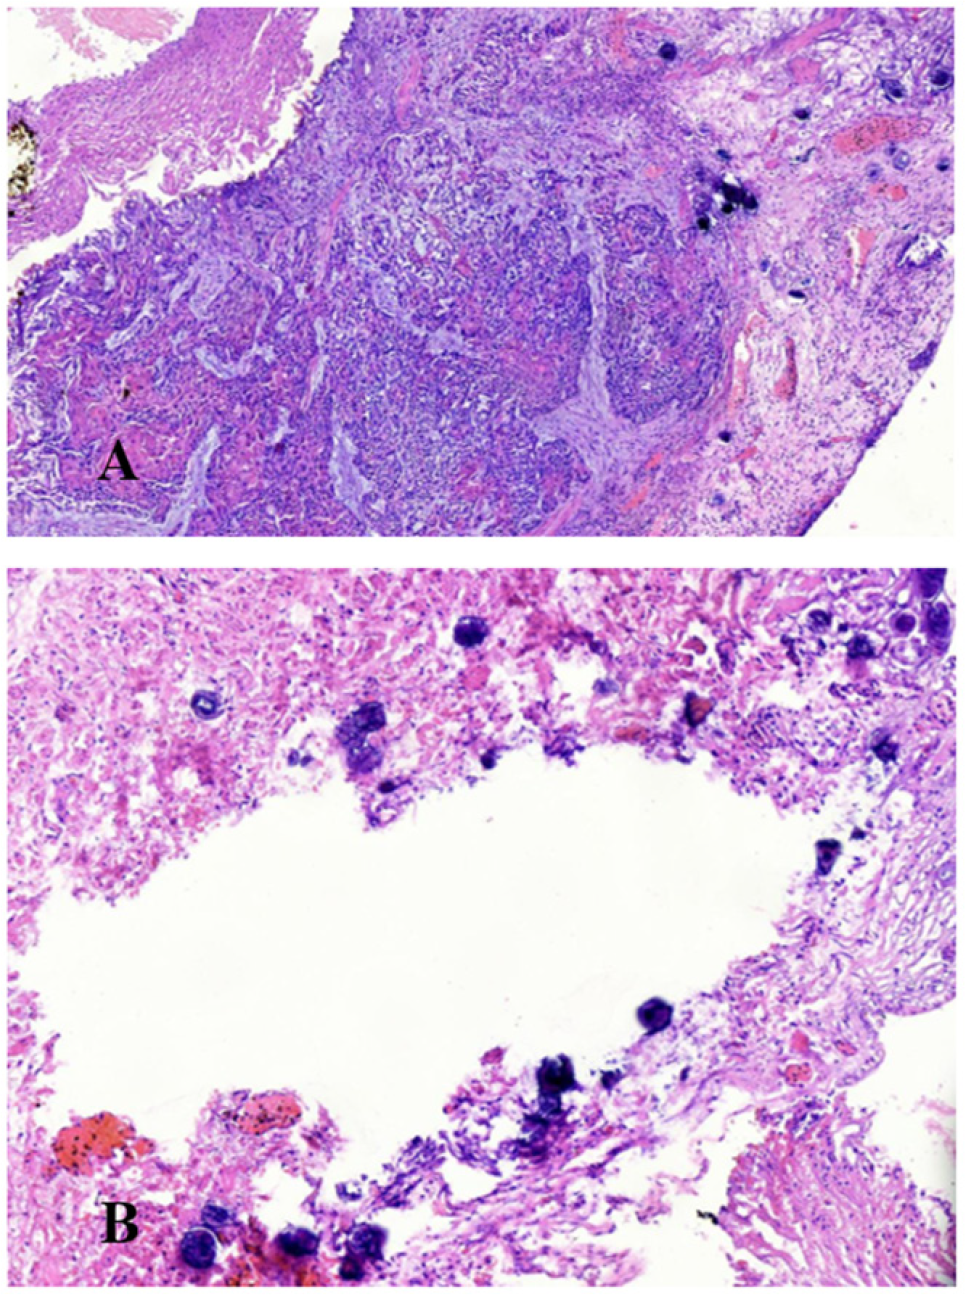

Results: A total of 162 cases of Transurethral resection of the prostate were included in the analysis. The mean age of the selected cases with transurethral resection of prostate was 69.19 (±9.14) years. In initial specimen, out of 162 selected cases, 42 (25.9%) were prostate cancer. The specific diagnoses included benign prostatic hyperplasia (BPH) (72.8%), adenocarcinoma (25.3%), Schistosomiasis (1.2%) and Squamous Cell Carcinoma (SCC) (0.6%). For residual specimen, 31.5% were prostate cancer. The specific diagnoses included BPH (66%), adenocarcinoma (30.9%), Schistosomiasis (1.2%) and SCC (0.6%). In both initial (43.9%) and residual (53.8%) specimens, Grade group 5 was prevalent. Most of the initial specimen showed tumor volume of 81 to 90% and most of the residual tumor volume was greater than 90%. Overall agreement in histological diagnoses between initial specimen and residual prostate chips was 93.2% with a kappa strength (κ) 0.79. For specific diagnosis the agreement was 97.6%, 91.5%, 100% and 100% for adenocarcinoma, BPH, schistosomiasis and SCC Grade 1 with Schistosomiasis respectively. With exception of Grade group 5, the rest of the Grade group had low Kappa value of 0.12. Agreement of tumor volumes was 83.3% with a kappa strength (κ) of 0.79.